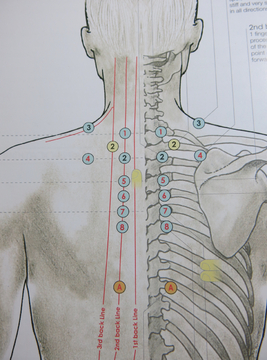

My holistic approach to manual therapy has developed over 10 years of studying and practicing various manual therapy techniques from East and West, including Sports Massage, Soft Tissue Therapy, Neuromuscular Technique (NMT), Soft Tissue Release (STR), Muscle Energy Technique (MET), Positional Release, Thai Yoga Massage (Northern style), Thai Acupressure Massage (Southern WatPo style), Thai Hot Herbal Massage, Medical Acupuncture, Kinesiotaping, Reiki. Whether you need to treat an injury or release tension, want to improve the flexibility of your muscles, prepare for a marathon or you simply want to relax, we will make the sessions meet your expectations. I am currently studying osteopathy in the University College of Osteopathy and Chinese Medicine and Acupuncture at the University of Westminster.

Lower Back Pain (osteothai) – Mudita School of Thai Yoga Massage (London)